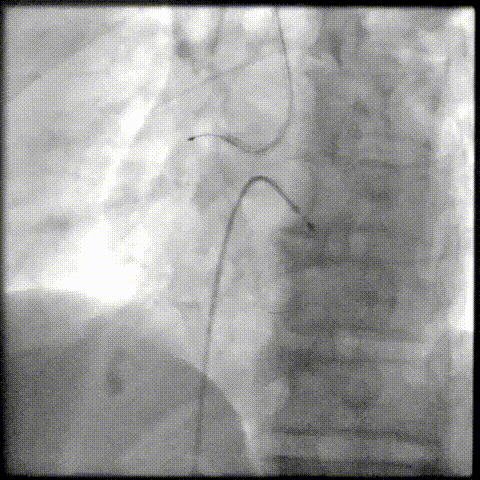

PCI过程-冲击波球囊PTCA

沿导丝送3.0×12mmGennWave冲击波球囊至RCA严重钙化病变处,充盈1:1比例造影剂盐水,以4atm低压扩张,每周期给予10秒、每秒1次血管内冲击波治疗后扩张至6atm,共进行8周期血管内冲击波治疗。

PCI过程-球囊PTCA

冲击波球囊完成后,进一步预处理,依次应用非顺应性球囊 2.75X15mm、非顺应性球囊 3.0X15mm、切割球囊 3.0X10mm等球囊反复由远及近进行扩张。